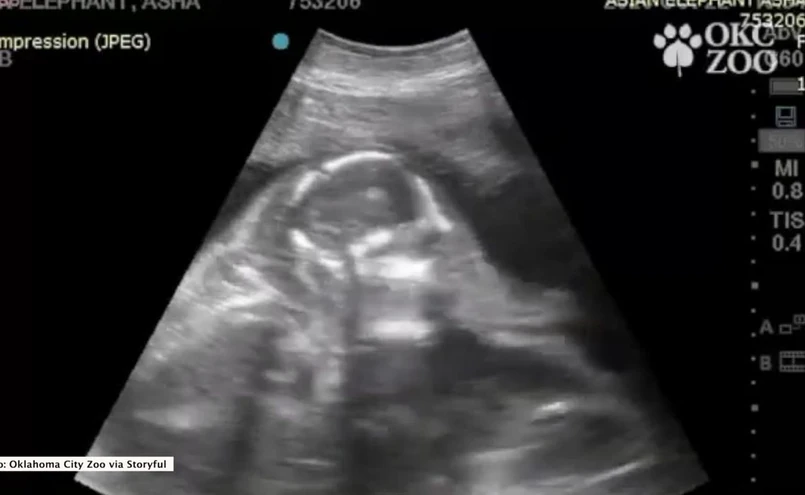

Zoo w Oklahomie podzieliło się nagraniem badania u słonicy Ashy, która jest w ciąży ze swoim czwartym słoniątkiem.

Poród przypada na luty 2022 roku. Słonie azjatyckie są gatunkiem zagrożonym wyginięciem, dlatego przyjście na świat tego malucha będzie wielkim wydarzeniem w placówce.